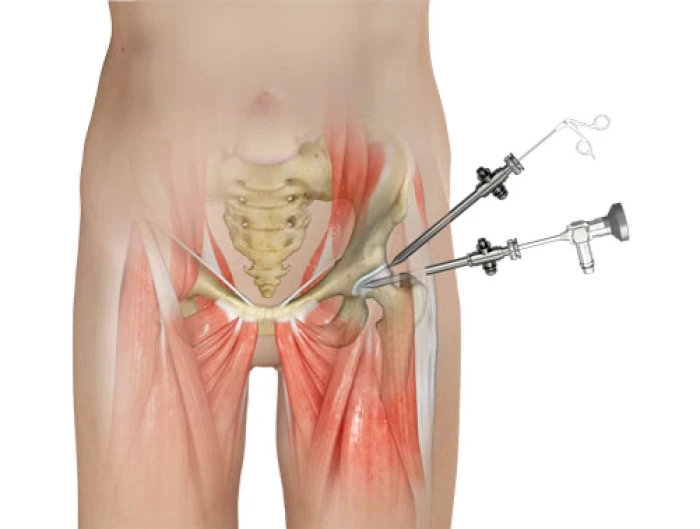

Técnica minimamente invasiva para tratar lesões internas do quadril com recuperação rápida.